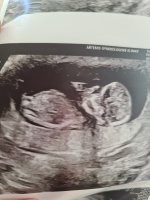

Vårt bilde var 99% jente, når vi sendte det inn. Skikkelig tydelig nub var det også.

Han er kjempe gutt.

Klart det!Interessant. Vil du dele bildet?